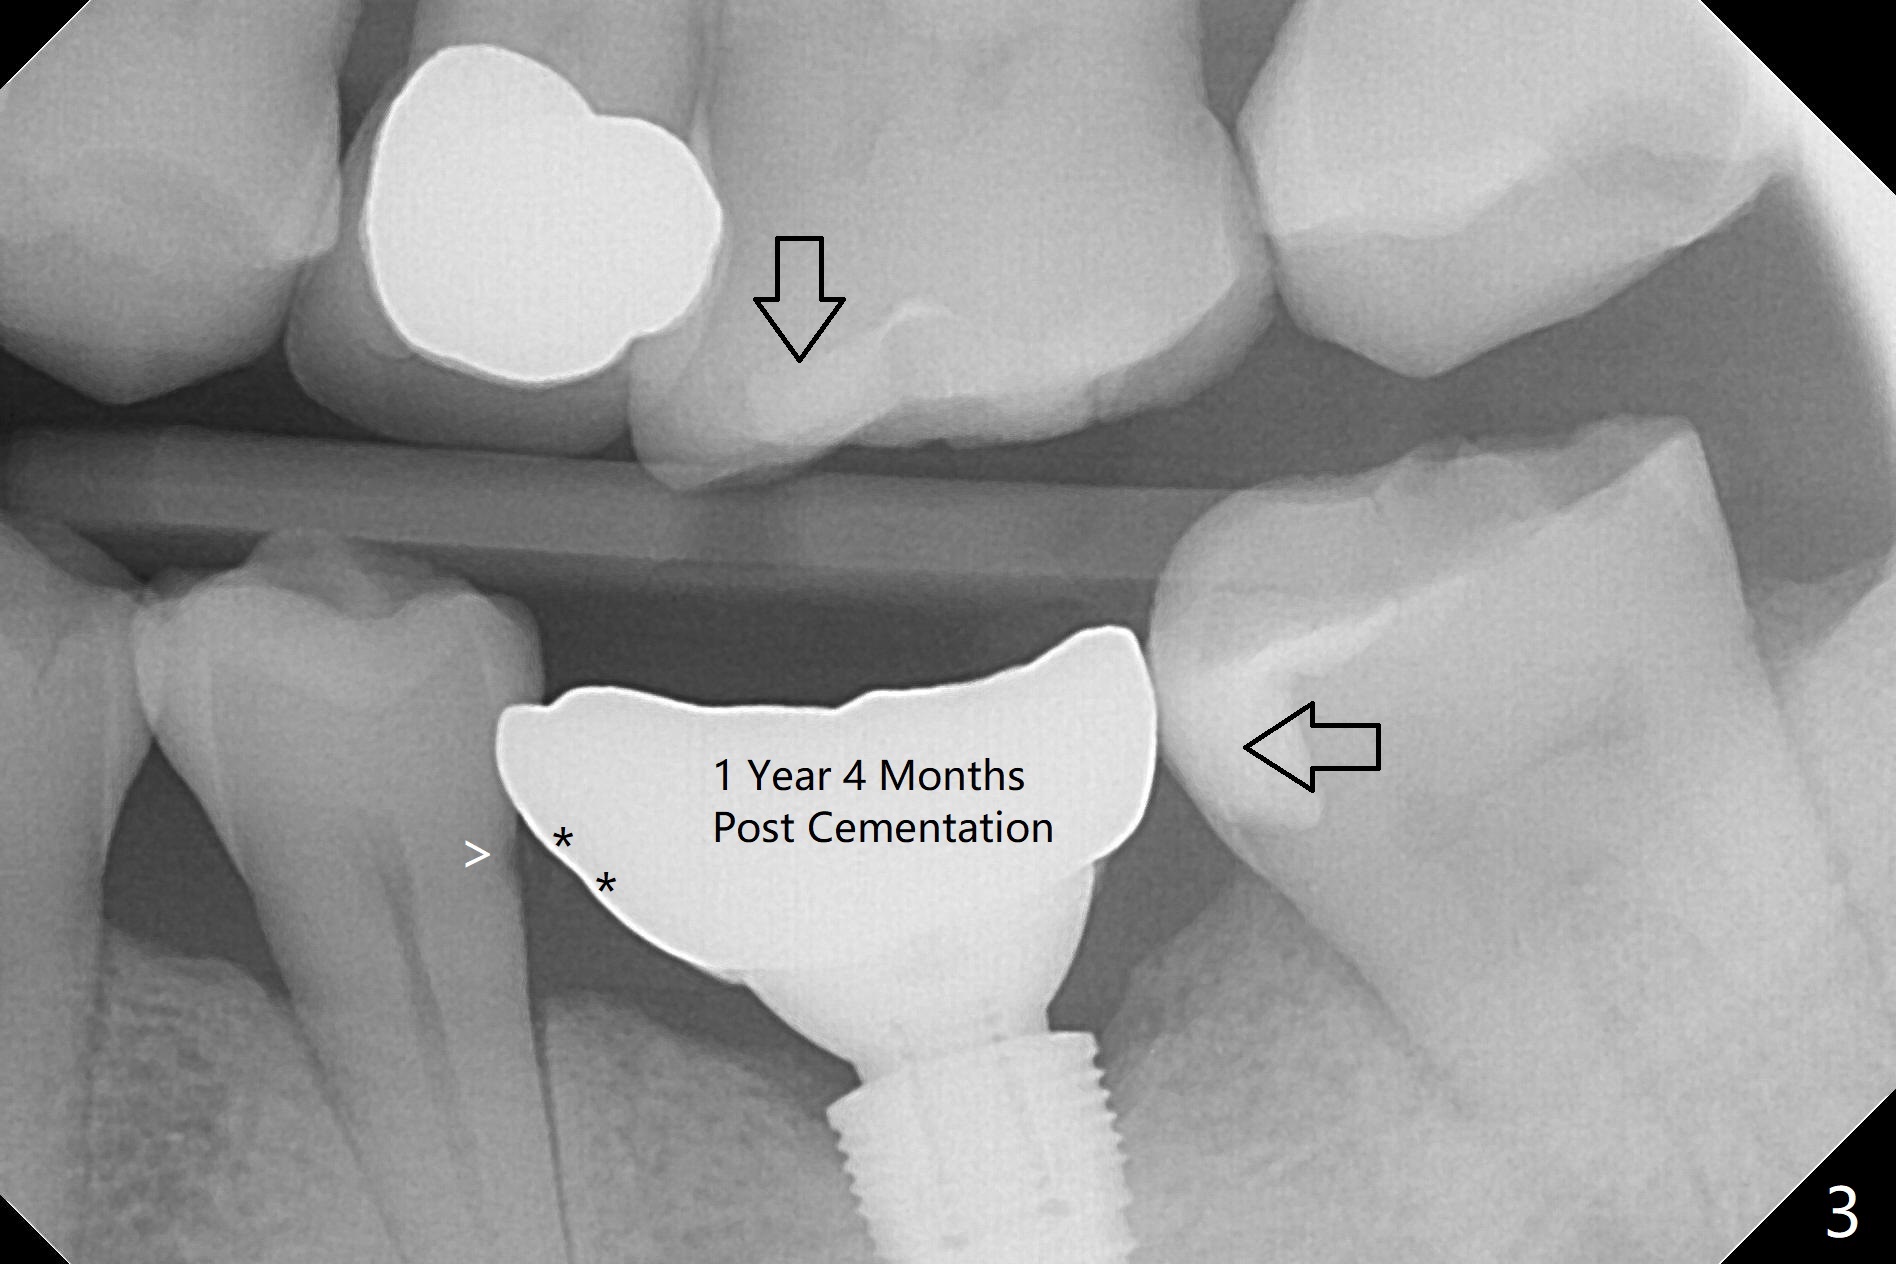

A 62-year-old man complains of food impaction around #19 implant crown one year 4 months post cementation (Fig.1-3). Before redo of the crown with poor mesial emergency profile (Fig.3 *), it appears necessary to correct the supraerupted opposing molar (Fig.1-3 downward arrow) and mesially tilted 2nd molar (Fig.3 horizontal arrow). The tooth #19 had been missing 20 years before implantation, associated with occlusal wear at #18 (Fig.4). For intrusion, composite is placed in the occlusal surface of #19 crown after roughening (Fig.5,6) with occlusal separation of the remaining dentition (Fig.6). The patient is instructed to bite on the left side as much and long as possible (even when he does not eat). Will the tooth #14 be intruded? Is the treatment sufficient?